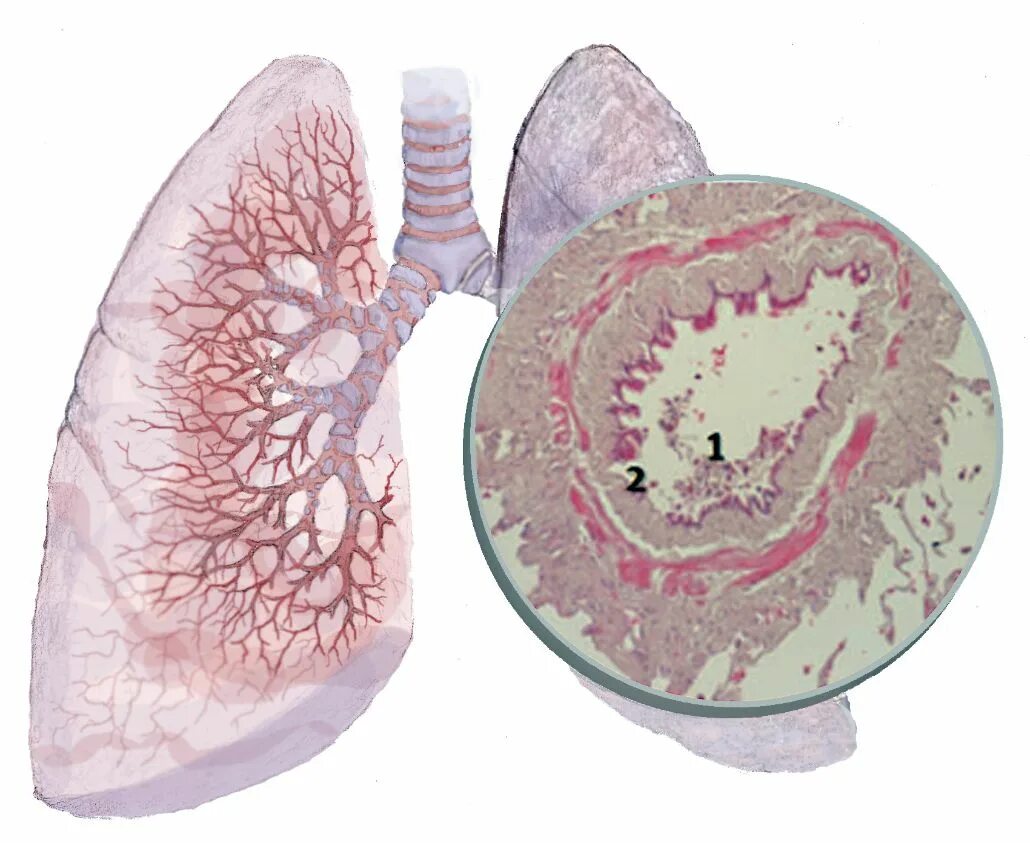

Дыхательная при пневмосклерозе